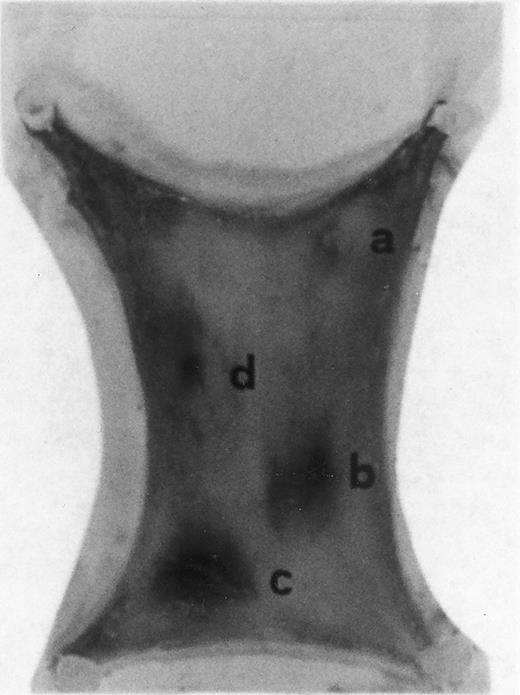

Evan's blue-stained intradermal injection sites showing the kinetics of the dermal response to exogenous human RANTES 10 ng/50 μL (c) and MCP-1 10 ng/50 μL (d); while (a) is a negative control (PBS 50 μL) and (b) is a positive control (FMLP 10−6 mol/L in 50 μL). This representative experiment was found to be reproducible and has been performed at least three times.

Intradermal injection sites of chemokines RANTES and MCP-1.In order to assess the inflammatory activities of RANTES and MCP-1 in an in vivo model we have injected 50 μL of these chemokines in four distinct sites of the abdomen of rats for the duration of 4 hours. At this time point animals were killed in accordance with previous data indicating that 4 hours is the optimal time for chemokine-induced chemoattraction.23-26 RANTES and MCP-1 were used at 10 ng/50 μL; while the chemoattractant peptide FMLP was used at 10−6 mol/L.8 In Fig 1 PBS (a, negative control) was not effective in promoting inflammation; RANTES at 10 ng/50 μL (c) enhanced dye extravasation at a greater extent than FMLP 10−6 mol/L (b, positive control); while MCP-1 at 10 ng/50 μL (d) was less effective than FMLP. In Table 1 we report a representative experiment with 12 treated rats. After chemokine challenge (4 hours) we calculated the mean ± S.D. of the major diameters (in mm) of dye extravasation at the site of injections (4 rats). Reported P values were obtained by comparing the effect of RANTES to MCP-1.